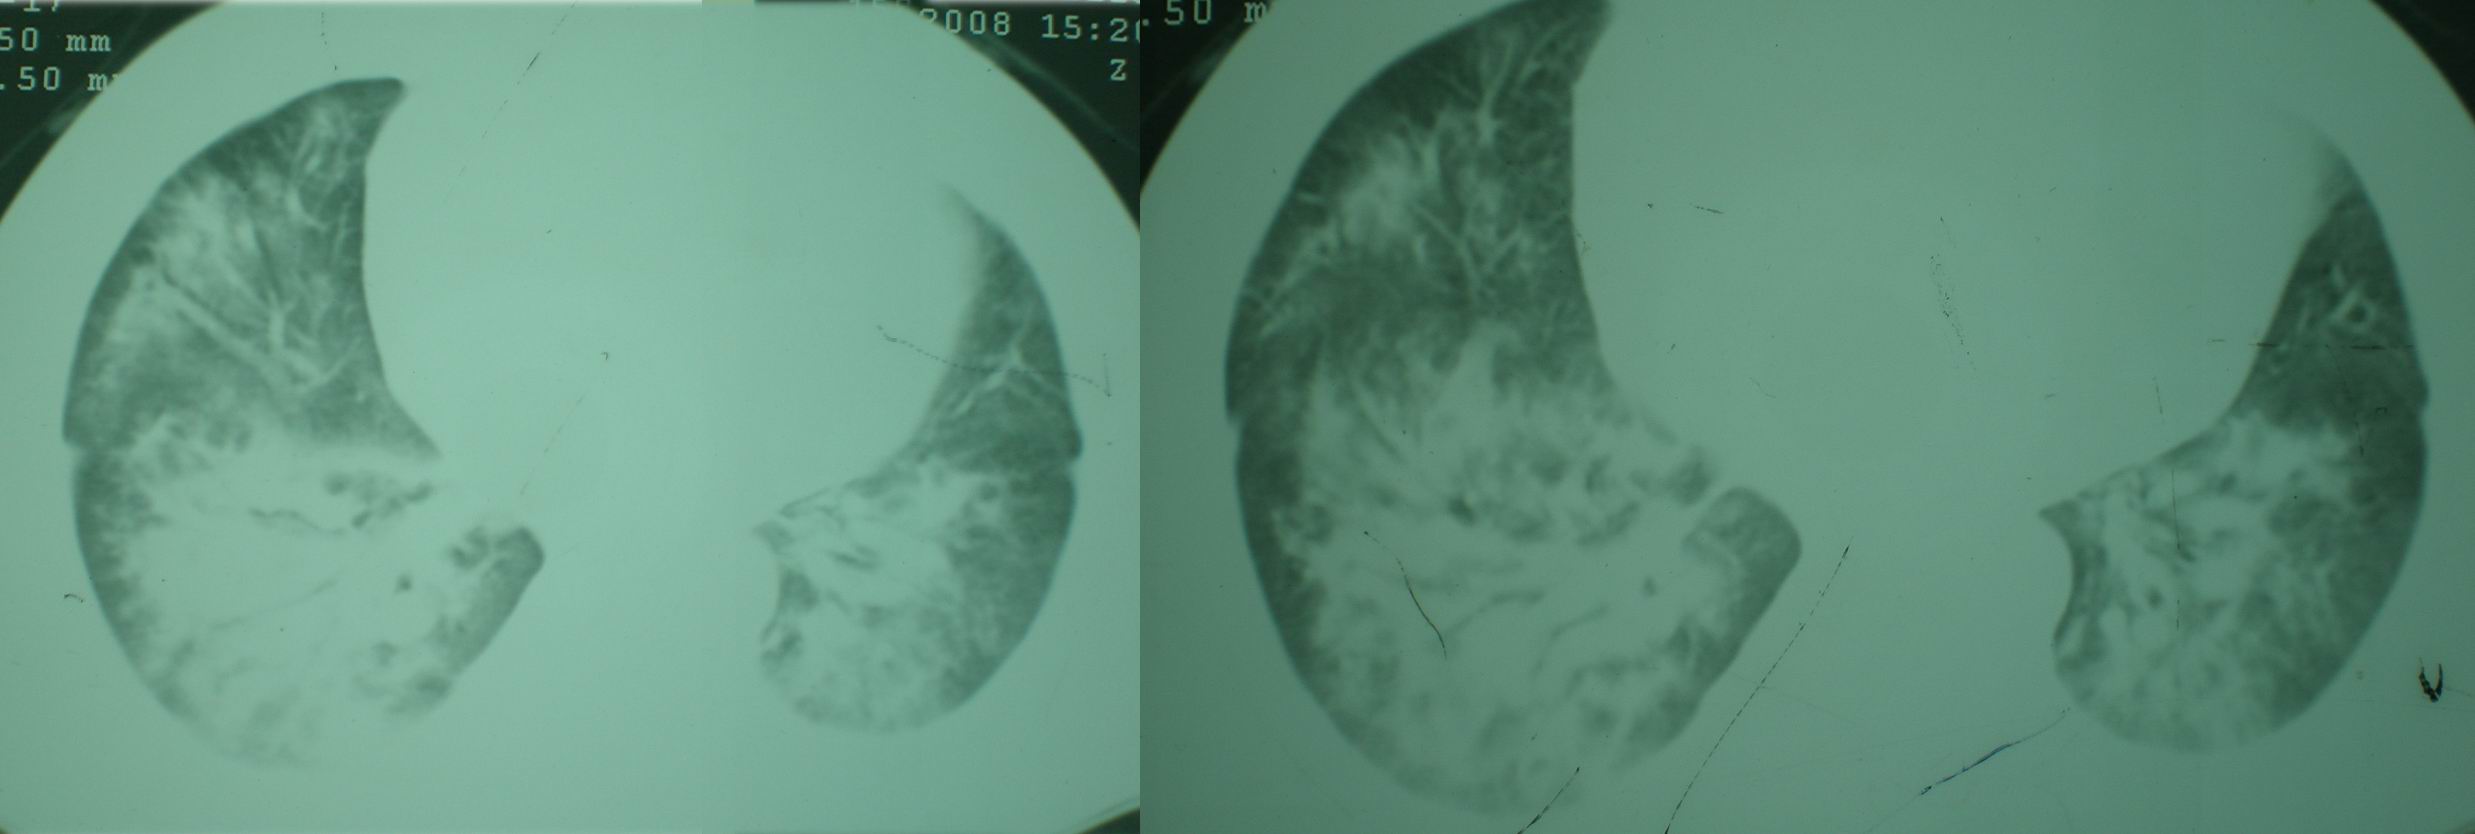

2008年11月18日今天的ct片

[face=宋体]显然上级医院进行了抗结核,抗真菌,抗炎等治疗,目前病人肺内病灶基本消失,双侧胸腔积液,右侧积液量有吸收,抗结核一个多月,现在病人疑问,结核的诊断是否有疑义,抗结核是否继续,因为那个毕竟副作用大。[/face]

我仔细看了下病人的出院小结,当时情况危急,诊断里有1型呼衰。心包周围的是脂肪密度。结合三次ct扫描的图象分析,个人认为:1、病人目前肺部病灶基本消失,双侧胸腔内少量积液,抗结核治疗才一个多月,就算是结核,抗结核治疗有效果,为何效果如此好,一点纤维灶的痕迹都没有呢,再就是患者做过气管镜检查及活检、痰检均未找到结核的证据。所以不支持结核的诊断。

2、结合现在的ct片,考虑:肺水肿及真菌感染,双侧胸腔积液。

机遇性感染。双肺实质满布。且以肺门周围为主。不象结核。